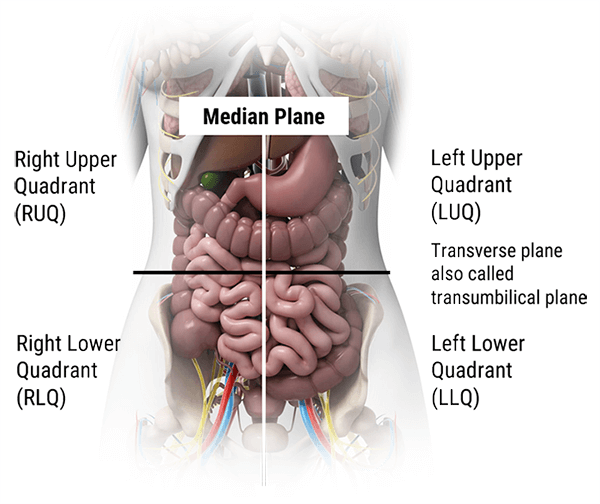

In this section we will explain how the abdominopelvic cavity is divided into 4 quadrants or 9 regions.

As shown in this diagram, the abdominal cavity has been divided into four quadrants: the right upper quadrant, the left upper quadrant, the right lower quadrant, and the left lower quadrant. These quadrants have different abdominal and pelvic organ systems. For example, the right upper quadrant contains the liver, gallbladder, and right colic flexure, whereas the right lower quadrant contains the appendix, terminal ileum, and right ovary in females.

The 4 quadrants are divided by 2 planes: the midsagittal plane and the horizontal plane at the level of the umbilicus.

- The navel also called belly button, the point at which the two planes cross, is the landmark you’ll use to visualize these quadrants while doing assessments

- The terms “left/right” and “upper/lower” are always from the perspective of the anatomical position, not your perspective. Be careful not to mix up your right and left regions, as this is where most students make a mistake!